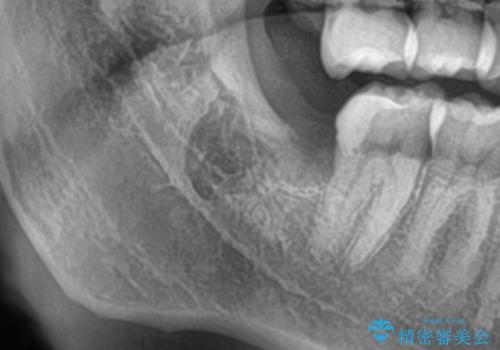

斜めに生えてきている親知らずを抜きたい

- 親知らずが虫歯になっている気がするとの事で来院。

親知らずとその手前の歯が虫歯になっていました。

先に虫歯を徹底的に取り除き親知らずを抜歯してe-maxインレーで治療を行いました。